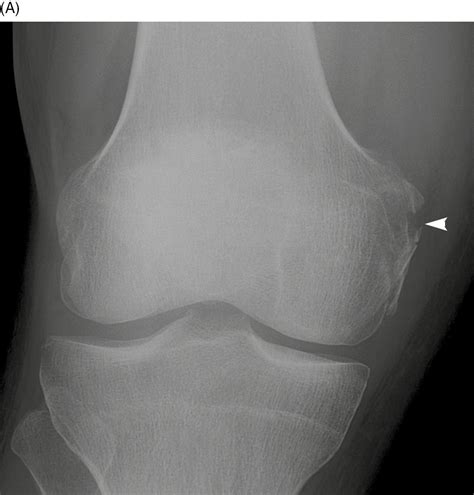

Lateral Condylar Fractures

These fractures typically occur due to high-impact trauma, such as car accidents or falls from significant heights. Because the lateral condyle is a major weight-bearing surface, fractures here can lead to joint incongruity, meaning the surface of the bone is no longer perfectly smooth. This often requires surgical intervention with plates and screws to restore the joint surface.

Osteochondral Lesions

An osteochondral lesion involves damage to the cartilage and the underlying bone. These can occur due to repetitive micro-trauma, common in high-impact sports like basketball or soccer. Athletes often report sharp pain, locking of the knee, or a sensation that the knee is “giving way.”